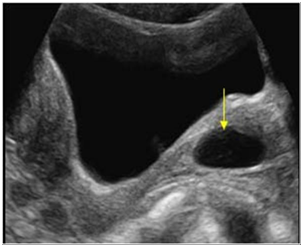

What pathology are we seeing in the cervix?

Cervical polyp